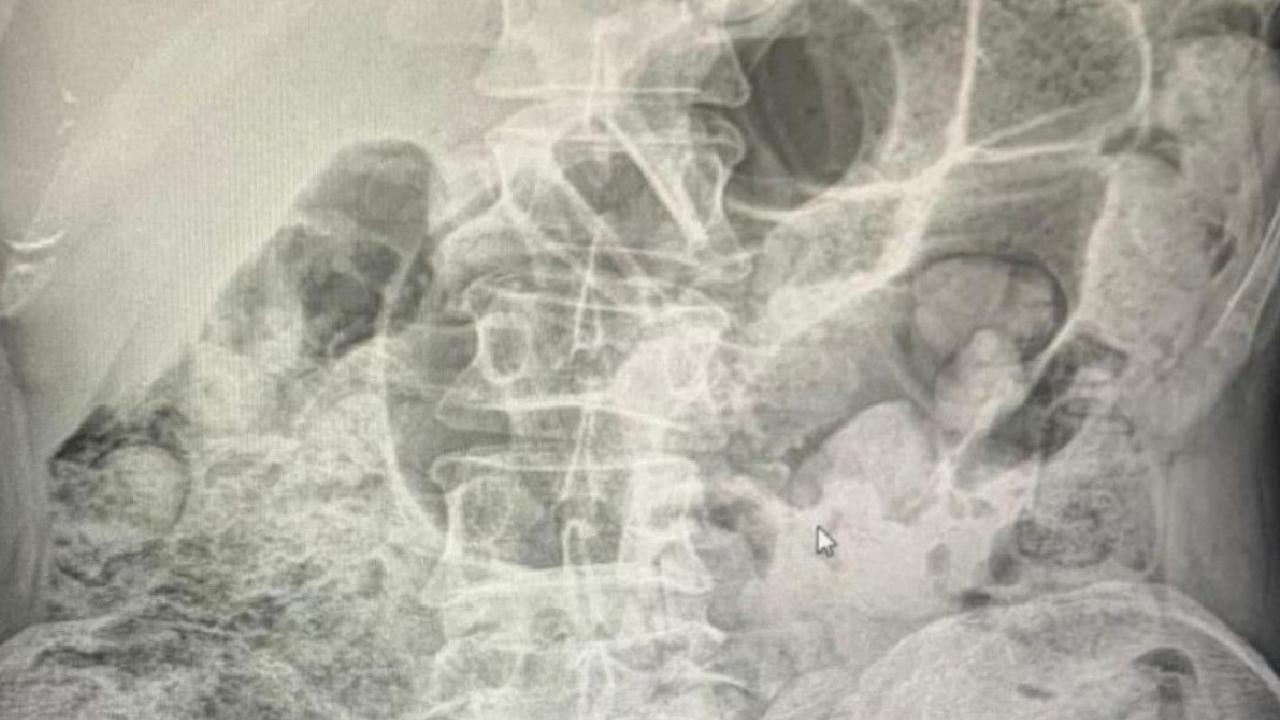

Yapılan radyolojik görüntülemeler neticesinde şüphelilerin midelerinde çok sayıda cisim olduğu belirlendi.

Zanlıların midelerinden 119 paket halinde 1 kilo 597 gram eroin ve metamfetamin çıkarıldı.